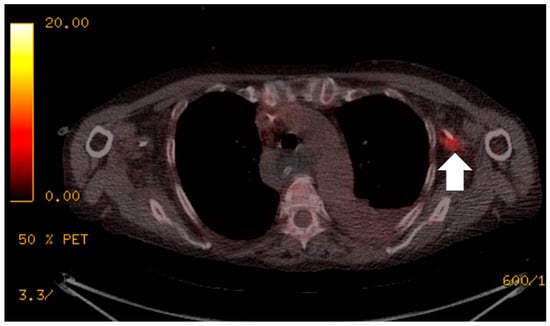

Figure 1. The patient presented with an elevated white cell count and raised C-reactive protein (CRP) of greater than 250 mg/L, but multiple previous image-guided drains, aspirations, line and blood cultures were negative. 18F-FDG PET/CT localised the infective focus to the left peripherally inserted central catheter (PICC) line (white arrow). The PICC line was removed and there was a subsequent improvement in the patient’s clinical condition.